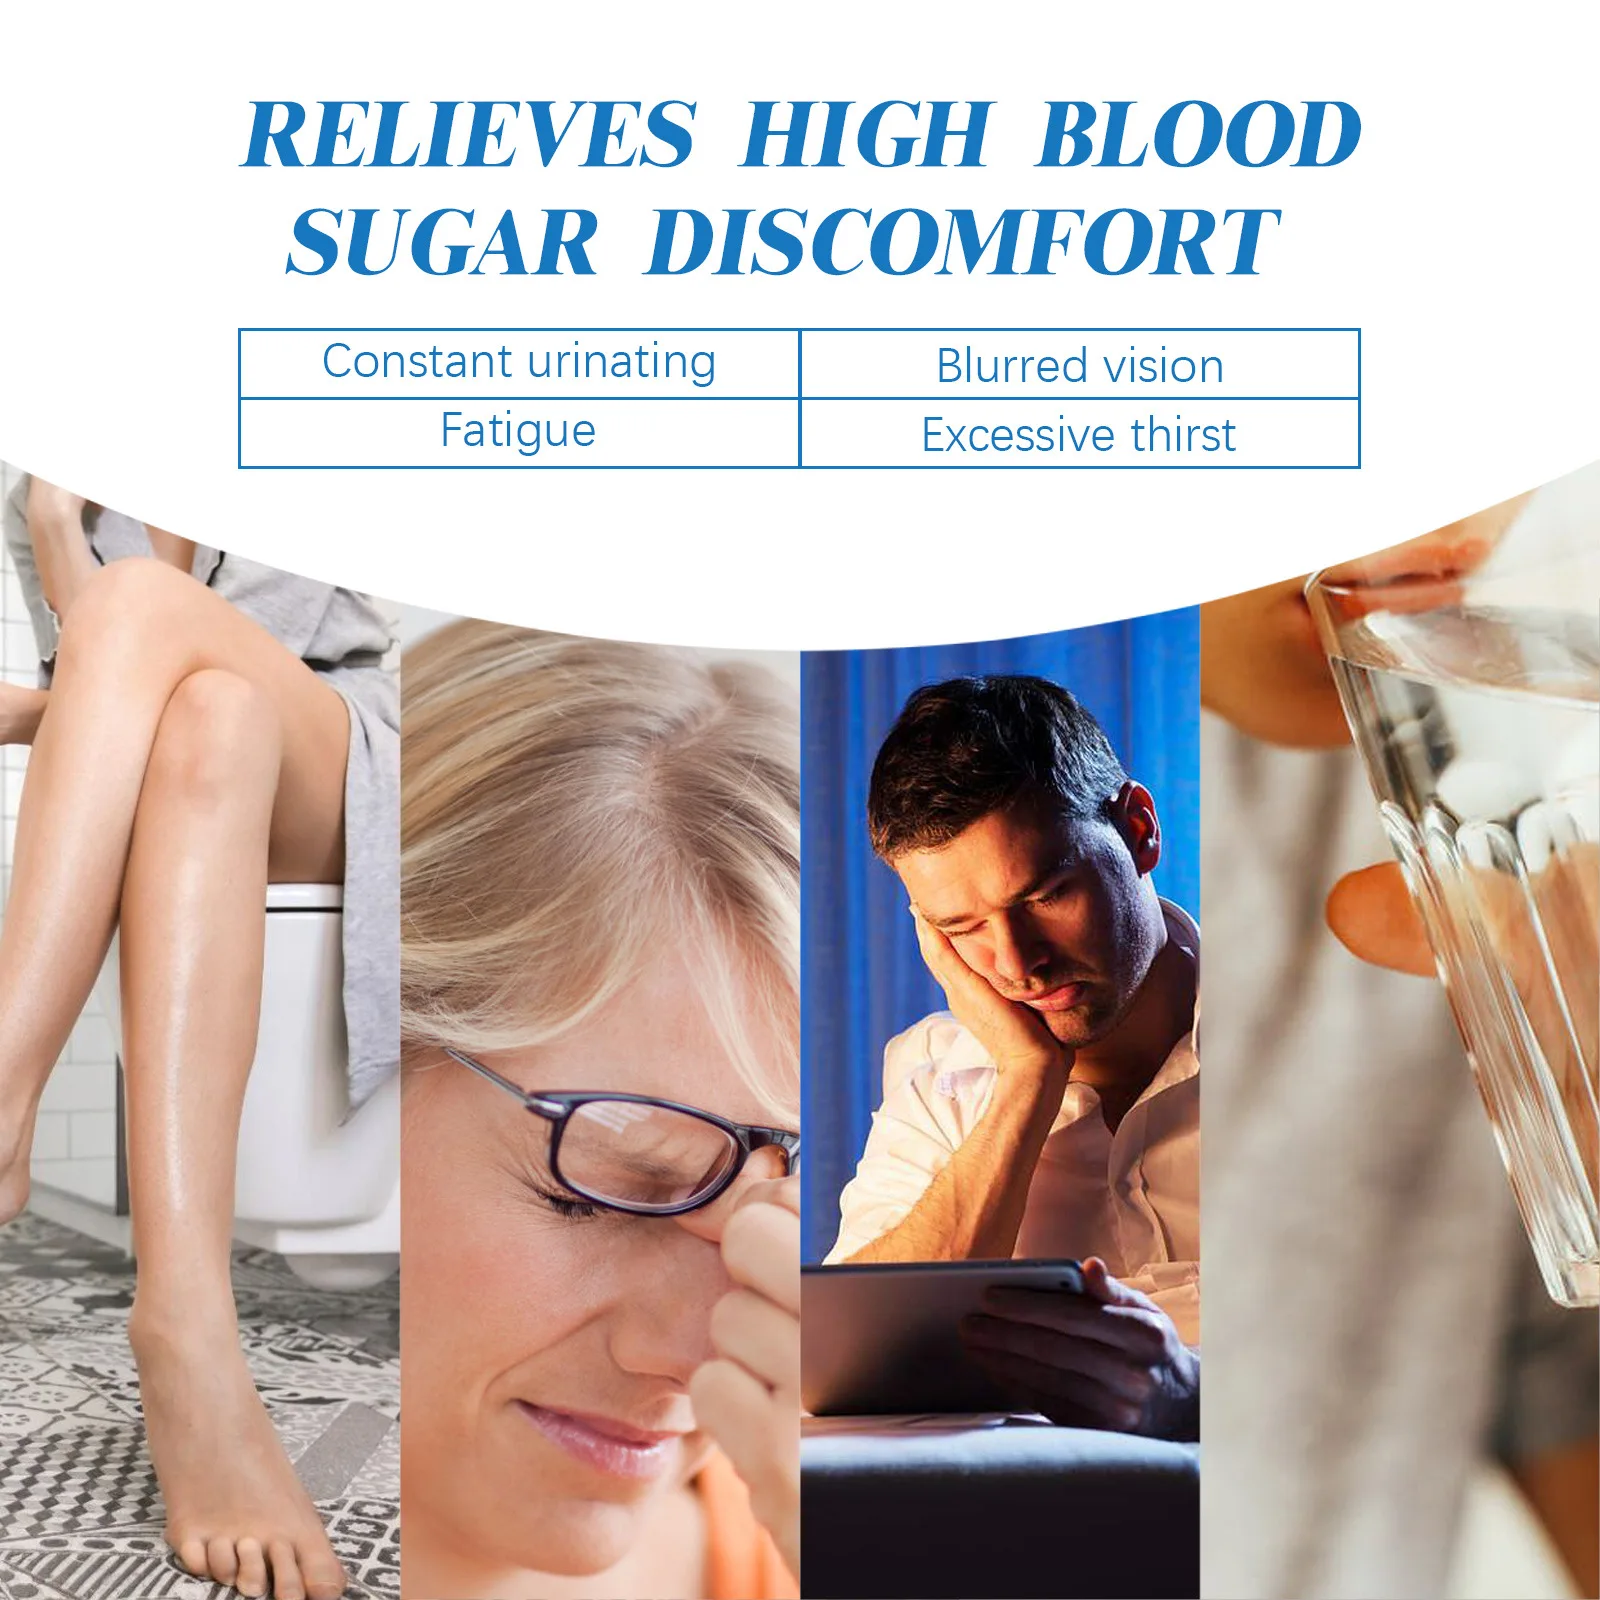

Effect: Sugar control

#Relieve Physical Discomfort Necklace

#Relief Nerve Pain Chain

#Relief Headaches Magnetic

#Relief Hyperglycemia Magnetic

#Healthy Energy Healing

#Health Necklace for Men